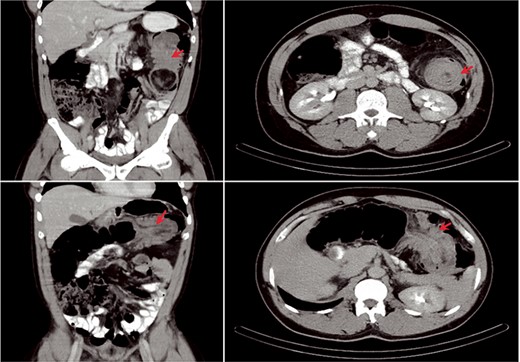

A 54-year-old man presented to his gastroenterologist with a 4-week history of worsening crampy abdominal pain associated with abdominal distention and obstipation. He was admitted urgently to the hospital after CT imaging revealed an evolving large bowel obstruction from transverse colonic intussusception likely secondary to a colonic mass lead point (Fig. 1). The patient underwent colonoscopy, but dusky nonviable mucosa was seen at the leading edge of the intussusceptum (Fig. 2), so no attempt was made to traverse it and the patient was taken for emergent surgical treatment. Using a hand-assisted laparoscopic approach, the cause of obstruction was confirmed to be a long segment of intussuscepted proximal transverse colon traversing the entire splenic flexure into descending colon, with a boggy mass acting as the lead point. The transverse colonic intussusceptum was carefully milked backward from within the descending colonic intussuscipiens to its natural anatomic position. Despite return of pink, viable colon appearance after a decompressive colotomy, some serosal abnormalities and congestion of the right colon from severe distention warranted its resection. An extended right hemicolectomy was performed with a distal transection margin 10 cm distal to the colonic mass origin, followed by stapled side-to-side, functional end-to-end ileocolonic anastomosis. The resected specimen was opened intraoperatively, revealing a large, pedunculated, polypoid mass with soft center consistent with colonic lipoma (Fig. 3). The patient recovered well, with return of bowel function on postoperative Day 3 prior to discharge home. Histopathology confirmed a 9.5 × 5.5 × 4.5 cm submucosal lipoma (Fig. 4) and 12 benign lymph nodes.

CT appearance of colonic intussusception (arrows) in the left upper quadrant secondary to colonic mass.